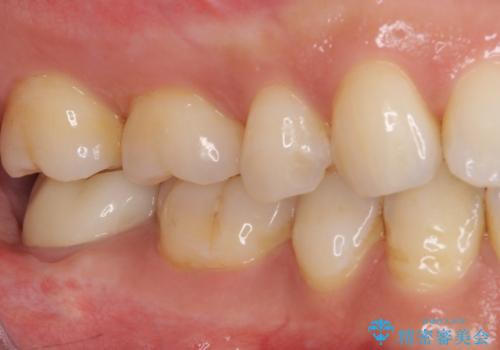

根管治療後の土台も構築されていたので、仮歯に置き換えた後にフルジルコニアクラウンにて補綴することとしました。

遠心の歯肉が盛り上がっていたため、清掃性が悪くなる懸念がありましたが、クラウン装着による歯肉の腫れは認められませんでした。